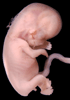

Carnegie Stage 23 (56 post-ovulatory days)

Most embryos at stage 23 are approximately 56-57 postovulatory days old and measure 23-32 mm in length. Distinguishing criteria for this stage include fusion of the eyelids at the medial and lateral margins, clear distinction of the subdivisions of the upper and lower limbs, the forearms appear at or above the level of the shoulders, the superficial vascular plexus of the head is very close to the vertex, and the external genitalia are well developed but not always sufficiently to distinguish the embryo's sex.

(NOTE: These specimens are late stage 23.)